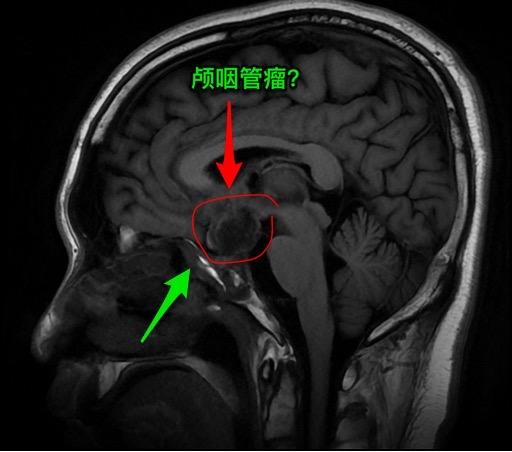

第一次经鼻手术后诊断为颅咽管瘤,可靠吗?27岁广西壮族自治区人,自幼视力不好。15个月前因多饮多尿、内分泌失调、视力下降在外院检查后诊断为颅咽管瘤,并作了经鼻内镜手术。取出一部分肿瘤内容物,病理报告为“角化物”。出院时诊断为“颅咽管瘤”。 一个月前患者又感视力下降,复查磁共振显示鞍区颅咽管瘤复发了,来找我作手术。头CT和磁共振见图。DWi显示肿瘤内容物呈白色,弥散受限,说明这不是颅咽管瘤。 手术中(我们采用开颅手术)看见肿瘤内容物为脱落角化上皮,其中未见毛发。将病灶囊皮及内